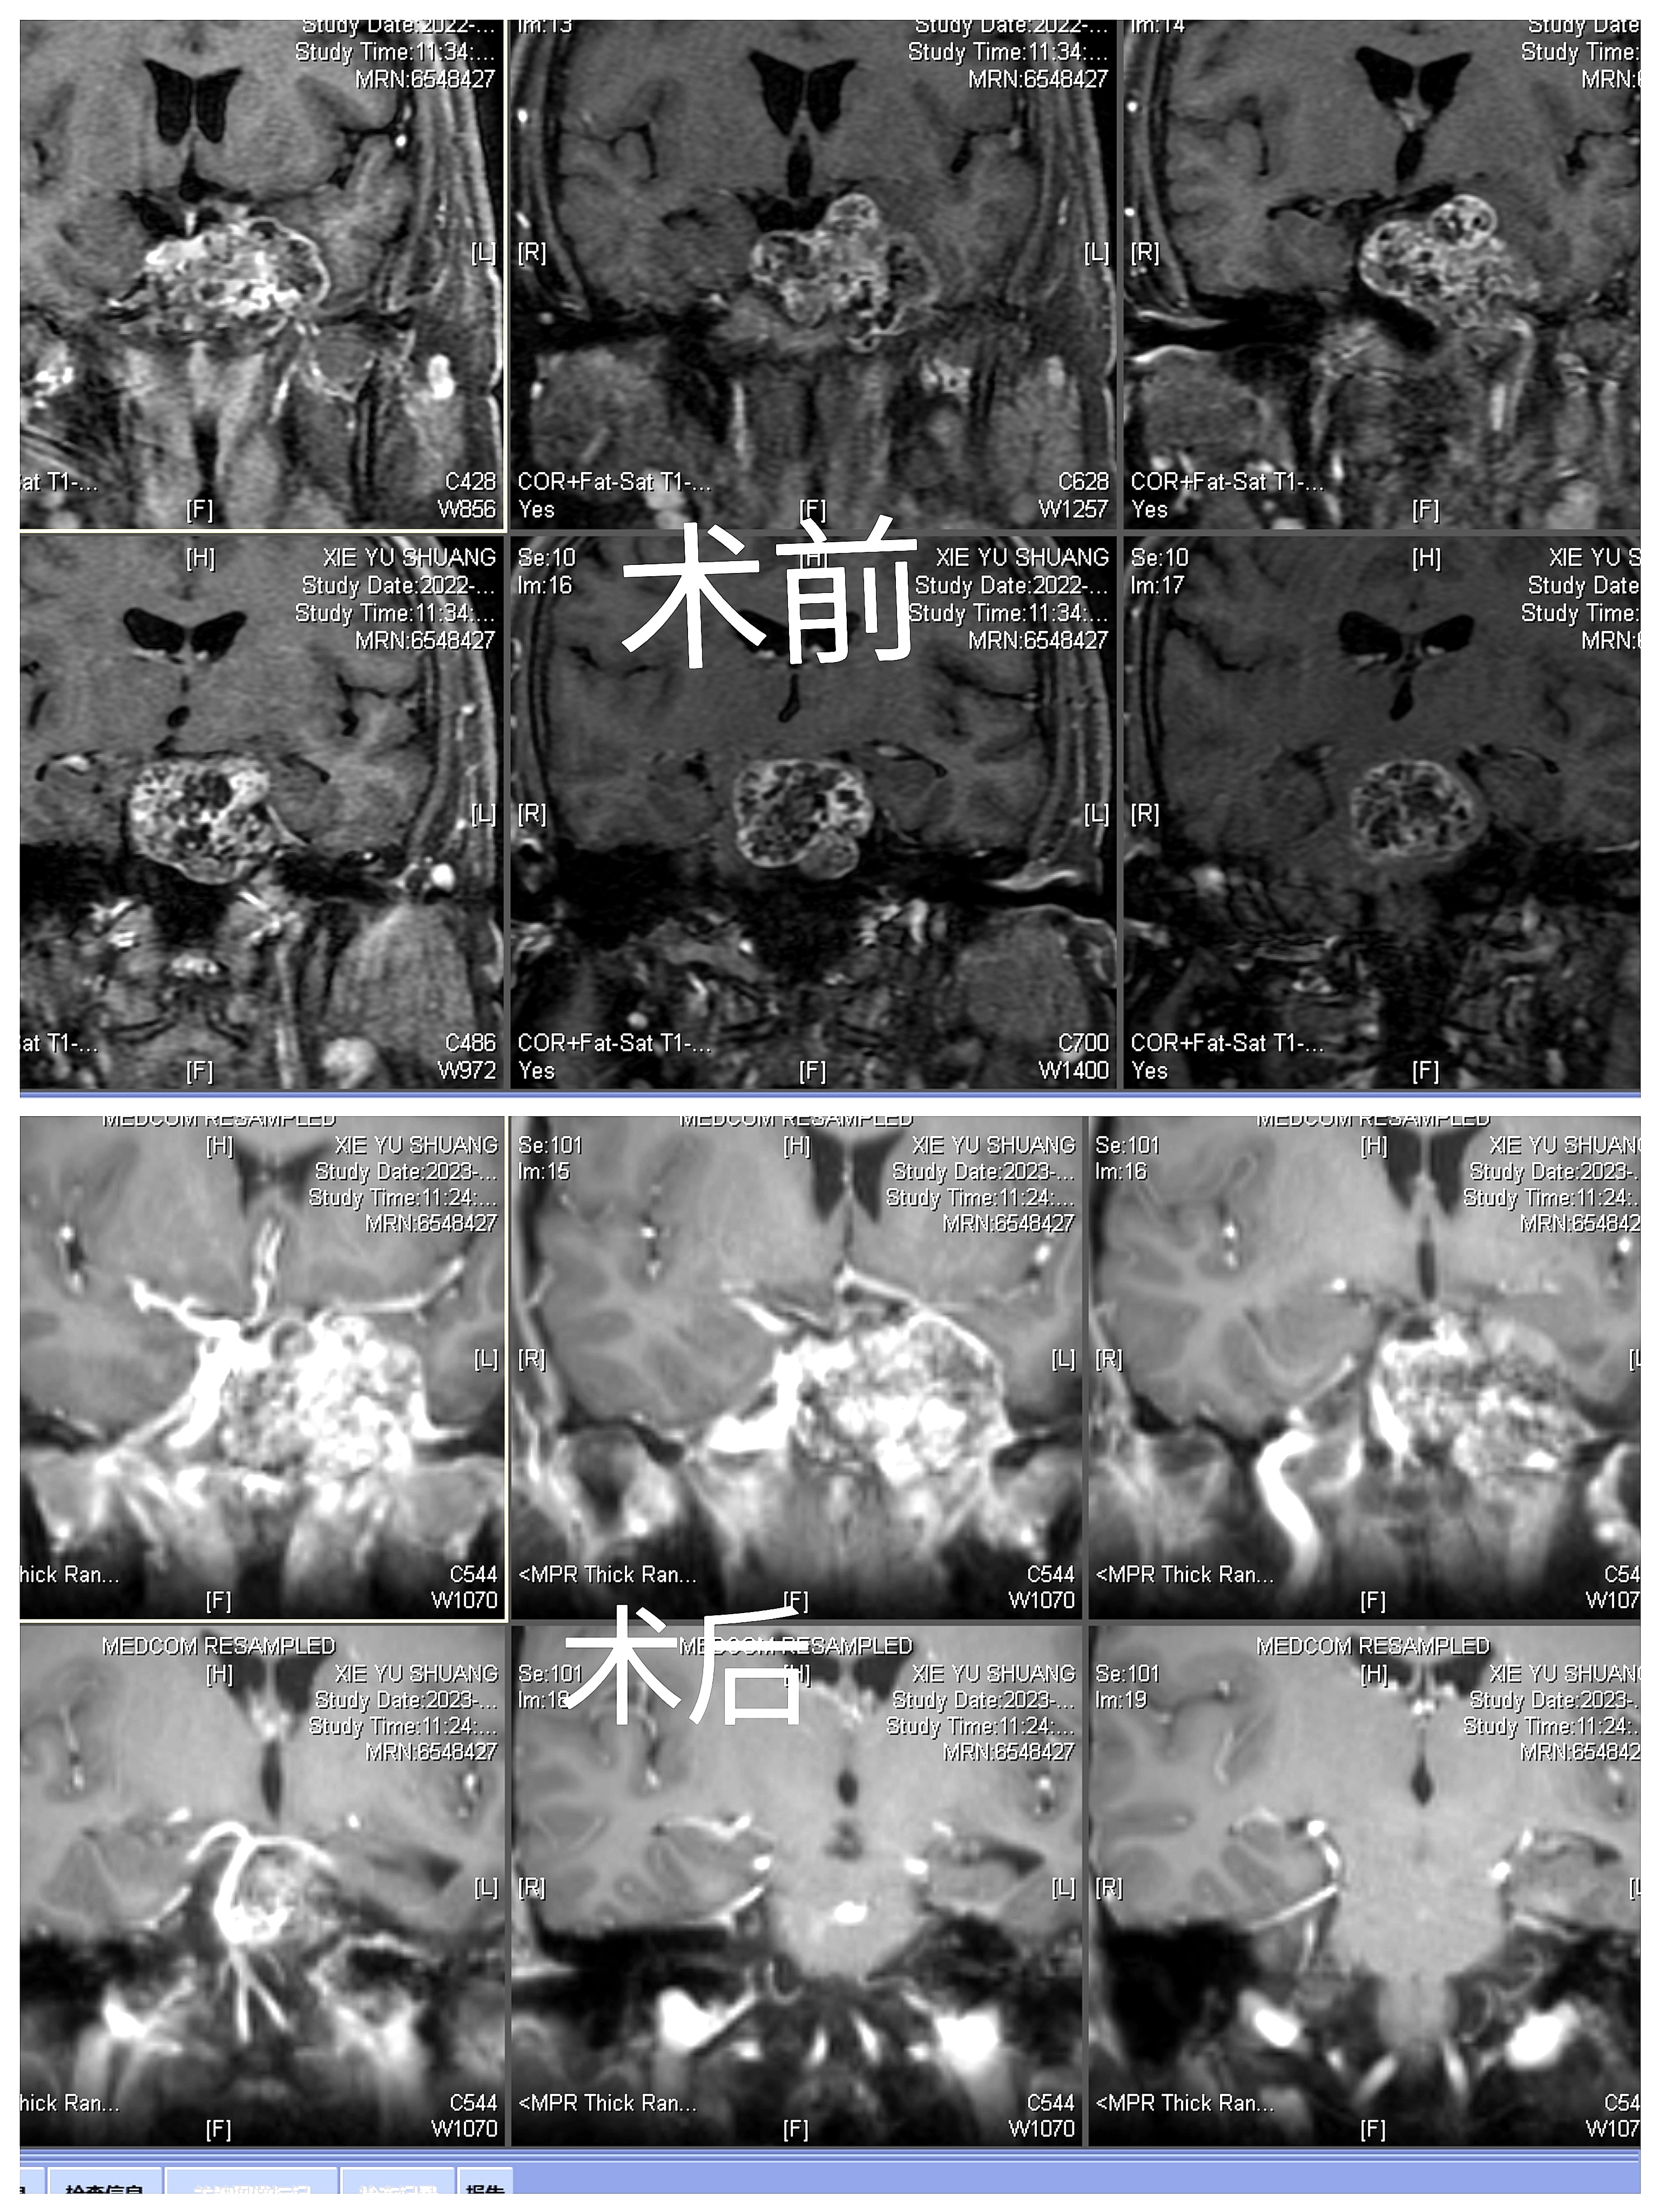

手术前

手术后